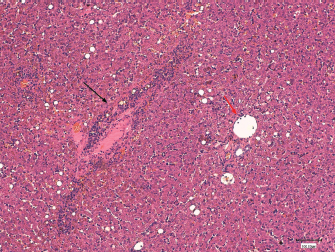

Ten out of the 17 biopsies were performed using a percutaneous approach (14 gauge true-cut needle biopsy), laparoscopy (using cup biopsy forceps) was performed in 6/17 and laparotomy was done in 1/17. The number of samples that were obtained ranged from one to two samples for cases in which true-cut needle biopsy was performed; and from one to five in all other techniques. The quality of samples obtained by percutaneous approach was classified as poor in 5/10, acceptable in 2/10, good in 2/10, and very good in 1/10. Those obtained by laparoscopy were mostly acceptable (poor=2; acceptable=3; good=1), and the surgical sample was estimated very good. The rhodanine staining pattern was centrilobular (zone 3) in 8/17 dogs (Figs. 3 and 4) and periportal (zone 1) in 3/17 dogs. In 6/17 dogs, the pattern was considered as multifocal.

Fig. 3. Histological section of canine liver. Haematoxylineosin stain. Magnification × 100, bar=100,100 μm. Hepatitis with centrolobular zone infiltrated by lymphocytes, plasma cells and a few neutrophils (black arrow). Normal portal space (red arrow).

Copper accumulation was confirmed in all clinical cases through rhodanine staining. The centrilobular stain pattern observed in the majority of dogs emphasizes the primary condition of the disease. This pattern is a recurrent finding in breeds in which the hereditary cause has been confirmed (Hoffmann et al., 2006). Periportal copper accumulation was observed in three dogs. This could be explained by the presence of periportal inflammation, hindering bile flow in this region. All these signs supports cholestasis, meaning that the accumulation of copper in those dogs, was likely to be secondary to the obstruction of bile flow. Finally, the multifocal copper accumulation was usually attributed by the pathologists to the overall low quality of the samples provided (small size, friability) and to a lesser degree to the marked structural modifications due to fibrosis. It can be concluded that copper can be distributed preferentially in zone 1 or 3, depending on the subjacent cause and occasionally be judged as multifocal due to either poor biopsy collection or advanced stage of the disease.